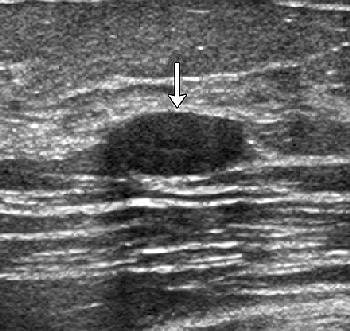

| Transverse images of fibroadenoma obtained in a 35-year-old woman during (a) conventional US and (b) tissue harmonic imaging. (a) A 1.0-cm oval-shaped slightly hypoechoic mass (arrow) is seen. (b) The mass (arrow) appears more hypoechoic and the circumscribed margin is clearly delineated. The final assessment by all readers was "probably benign" at both conventional US and tissue harmonic imaging. |